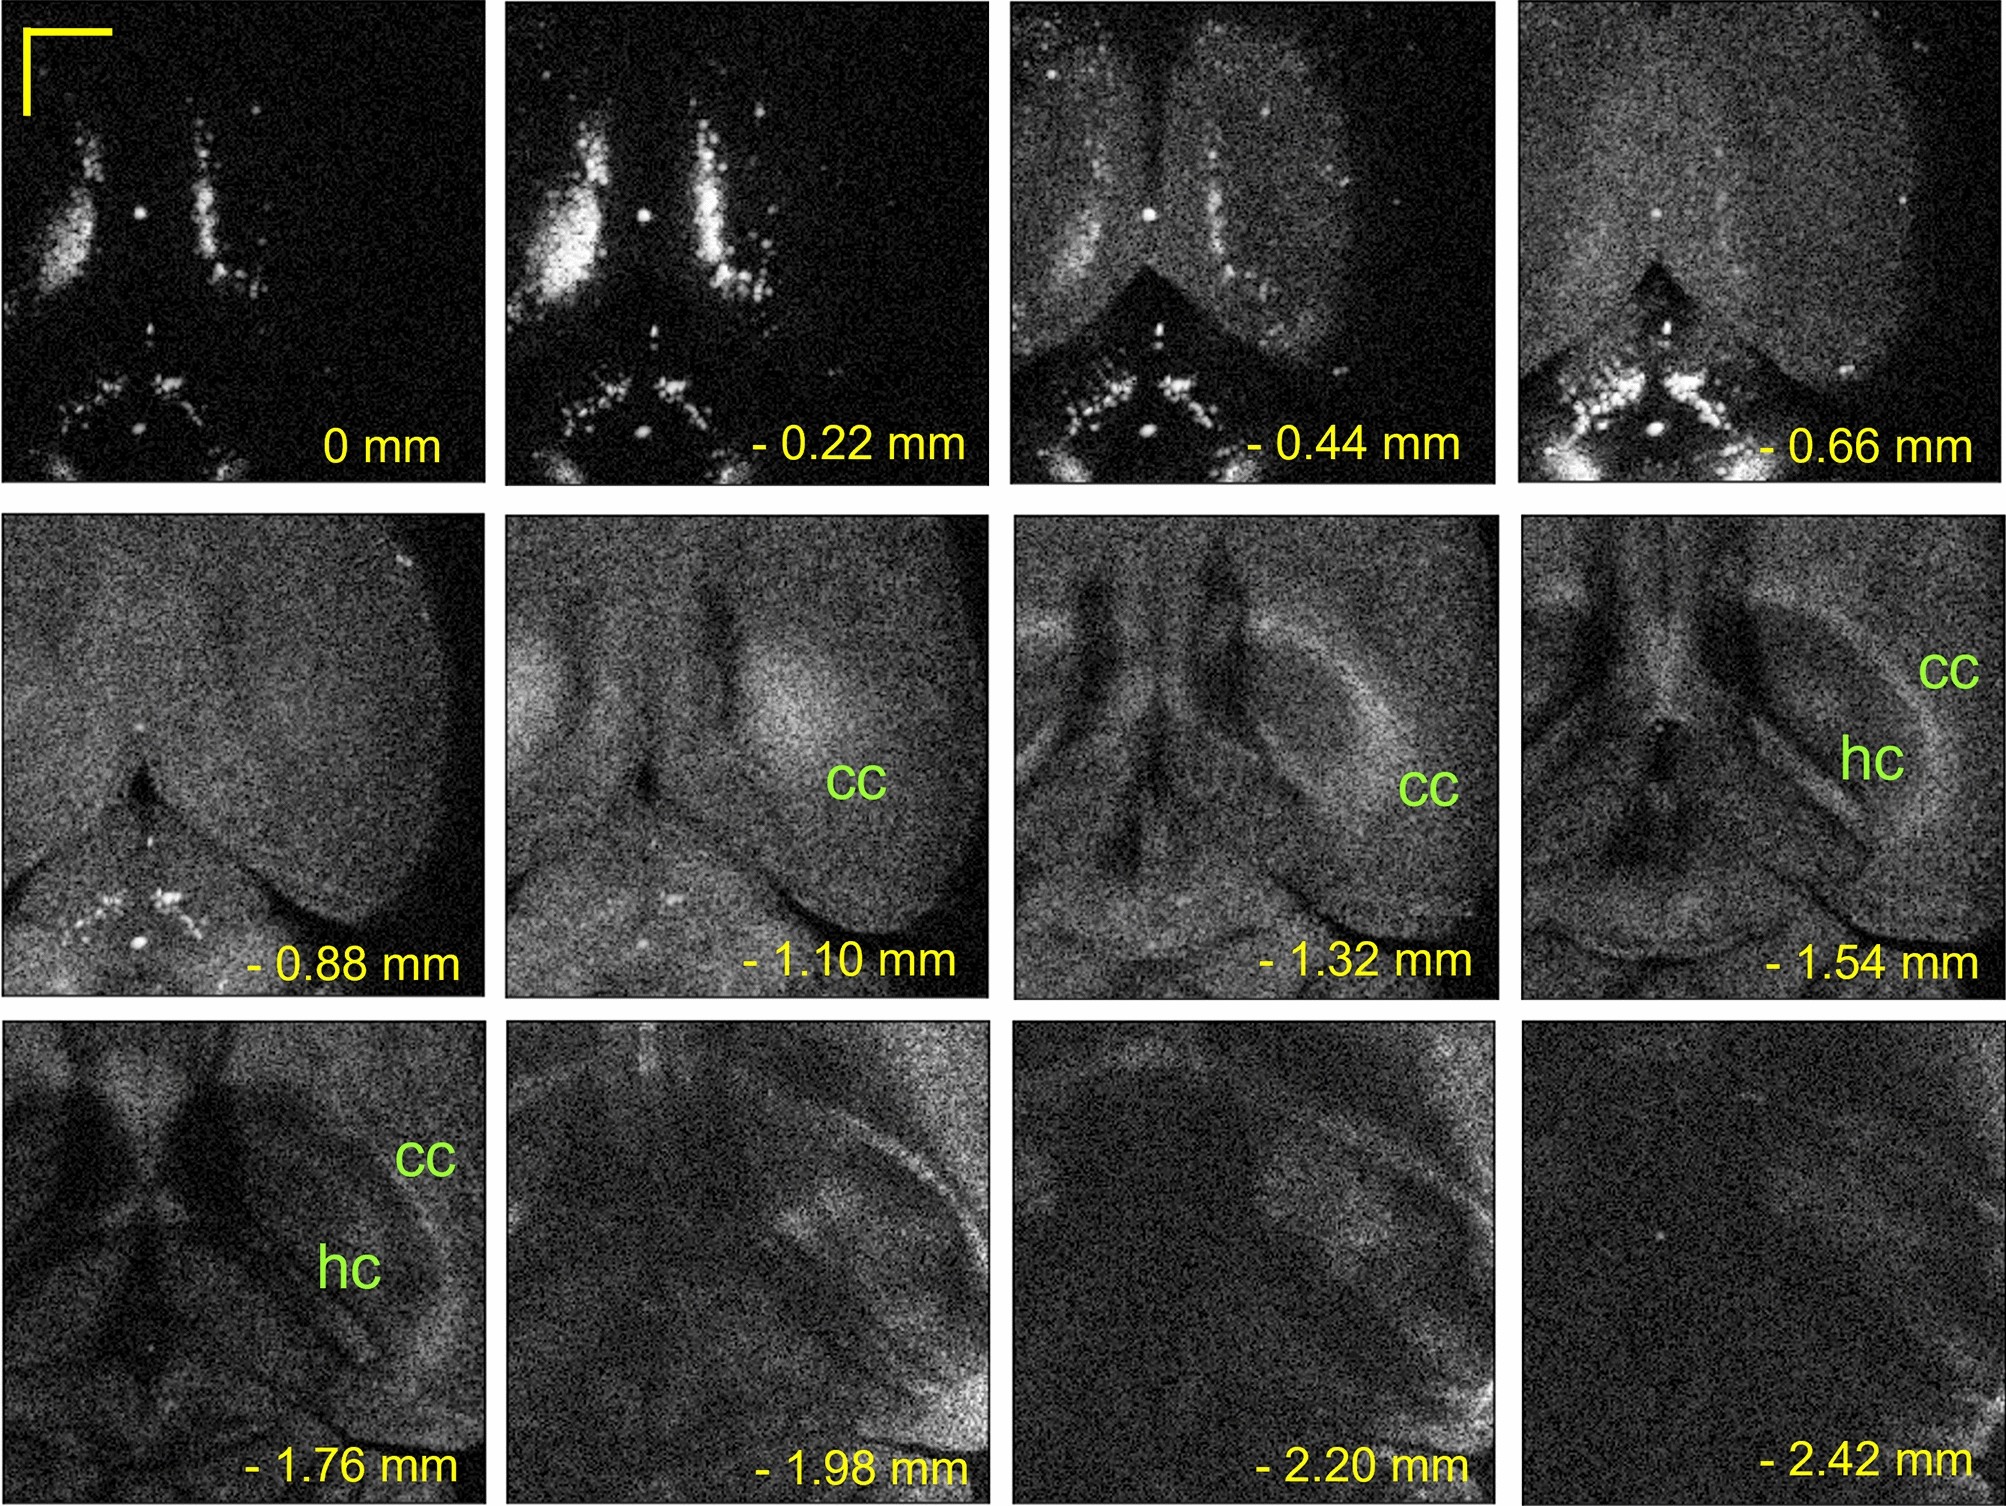

Figure 7

Bx − By scan images in various depths from the brain cortical surface. At the depth of 0 ~ 1.98 mm (2.20 mm and 2.42 mm), images were acquired with a Bx scan rate of 3 Hz (1 Hz). cc: corpus callosum, hc: hippocampus. Scale bar: 1.0 mm.